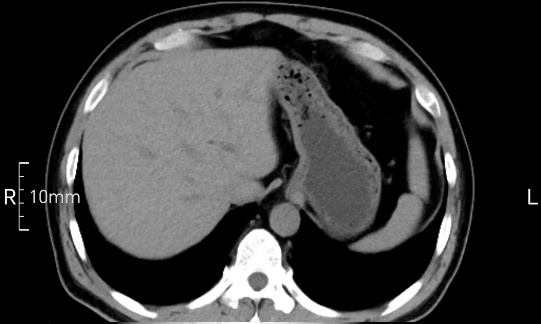

看看下面三幅便知遵醫囑的重要性。

完美禁食且喝飽飽,胃壁完美展現。

CT檢查前的“禁食”和“喝飽”,看似矛盾,實則合情合理,分工合作:空腹:是為了讓上腹部(肝膽胰脾腎等)的圖像清晰無干擾,并保障檢查安全。喝水:有效的充盈胃部和、腸道使圖像清晰呈現。兩者巧妙配合,都是為了給您一個最精準的診斷結果。